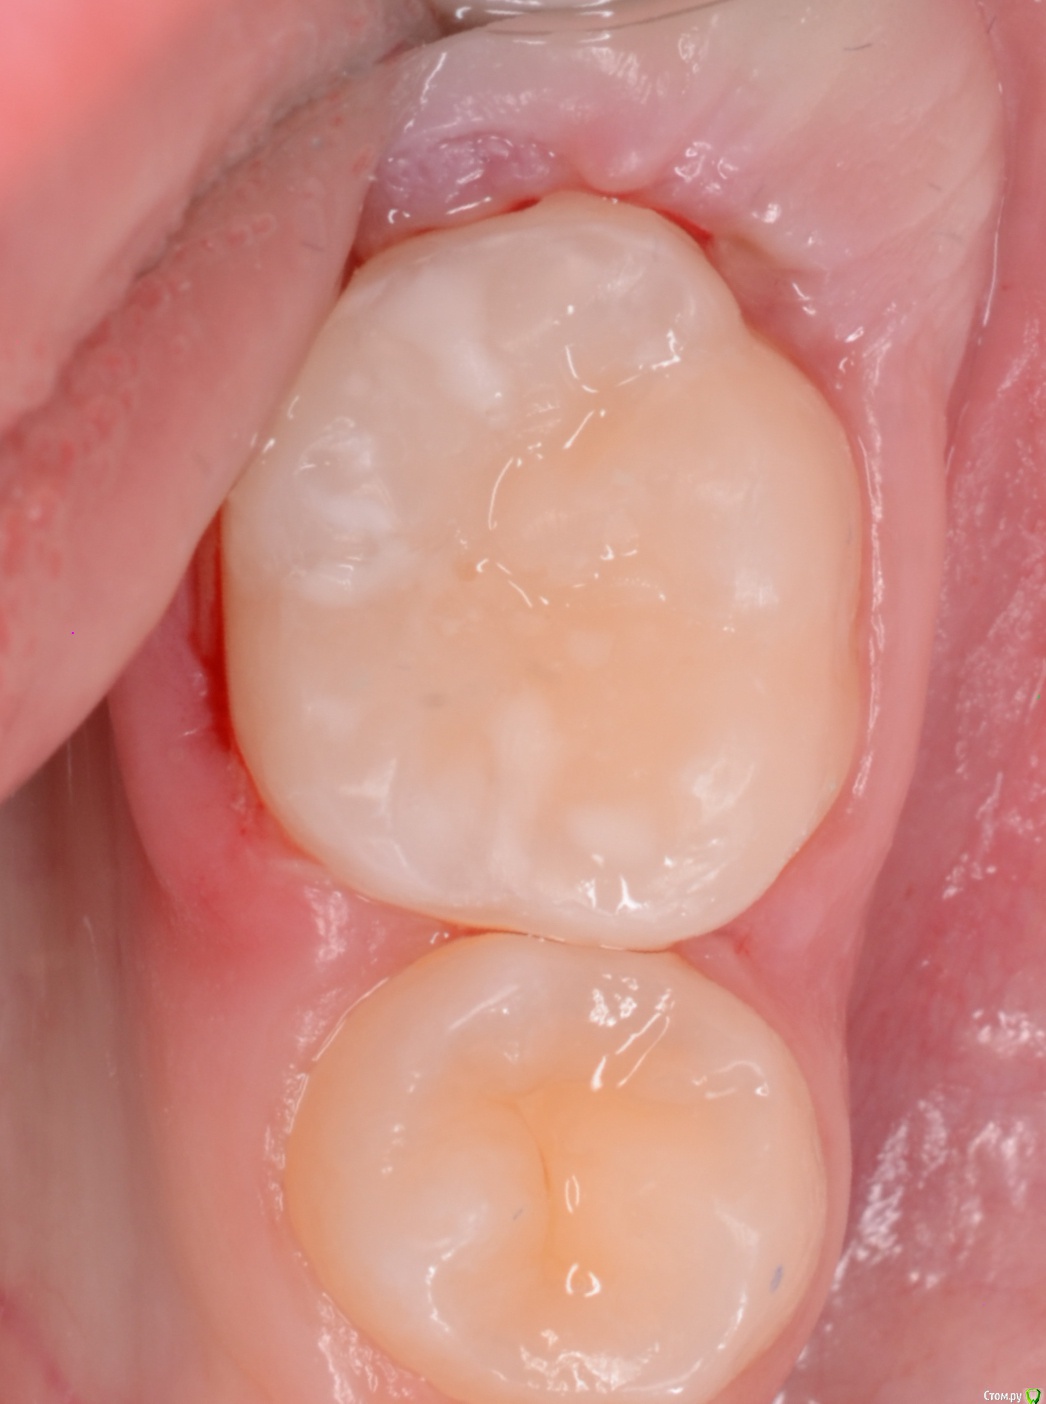

CRAZYDUCK Опубликовано 24 мая, 2018 Автор Поделиться Опубликовано 24 мая, 2018 В этом клиническом случае хочу обратить внимание коллег на покрытие 8.5 зуба коронкой ( что необычного видите ?). И на использование флосса, чтобы заправить платок дистально за 4.6 . 4.6 начальный кариес , но зуб дистально ещё был прикрыт десной ( фото до лечения не делала без коффердама). Раньше во время работы в эту дистальную зону «трамбовала» Фумку . Следила , чтобы не подтекало . Но !!!!Очень удобно эту десну заправлять флоссом - ничего не течёт 1 Ссылка на комментарий

CRAZYDUCK Опубликовано 24 мая, 2018 Автор Поделиться Опубликовано 24 мая, 2018 8.5 ранее лечен методом витальной ампутации( 1,5 года назад ), но реставрация обширная . Не выдерживает жевательную нагрузку . 2 Ссылка на комментарий

CRAZYDUCK Опубликовано 24 мая, 2018 Автор Поделиться Опубликовано 24 мая, 2018 Я всегда перед лечением очищаю зубы кавопрофифлекс ( все зубы , которые попали в зону изоляции ), поэтому изначально планировали только покрыть 8.5 коронкой . Из-за этого изоляция такая ( никакая), но после чистки 4.6 стало ясно , что планы немного меняются . Ссылка на комментарий